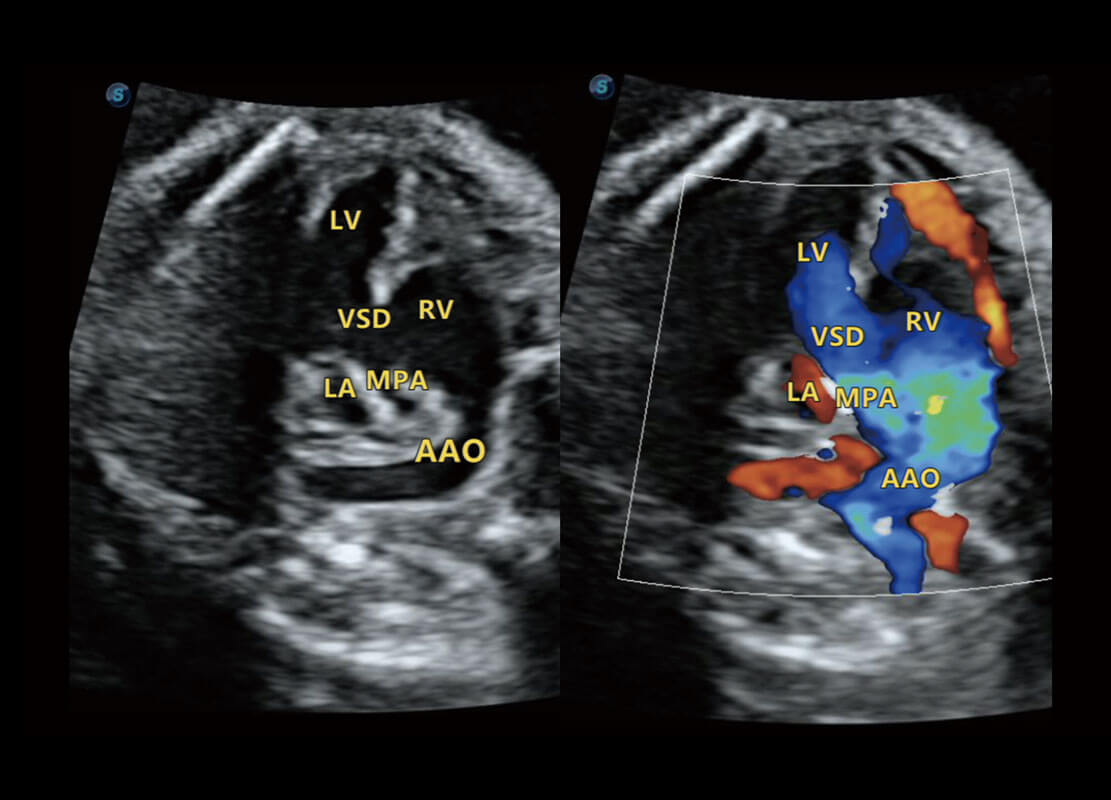

• 右室双出口

P60搭载一系列胎儿心脏成像技术,实现精细的胎儿心脏评估。